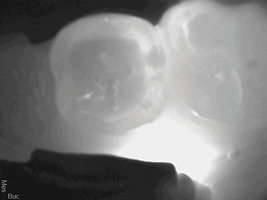

A 38-year-old female patient with incipient decay discovered on a transillumination caries detection device image (Figure 5 and Figure 6) presented for her bi-annual hygiene visit. The doctor was considering whether to treat the decay with a restoration or to "watch it." He decided that instead of monitoring the lesion, he could treat it with silver diamine fluoride, possibly halting the decay and hardening the lesion. The patient was informed of the possibility the decay would turn black; however, the decay process could halt, and she would not need a filling in the future. She was pleased at the prospect her tooth would remain intact without needing restorative treatment. After signing the consent form, she opted for treatment that day in the hygiene visit. She was appointed for one week later for the re-application of the silver diamine fluoride and advised that it may need to be reapplied one to two times per year.

(5.)  Incipient decay on tooth No. 29.

Figure 5

(6)  Incipient decay on tooth No. 20.

Figure 6